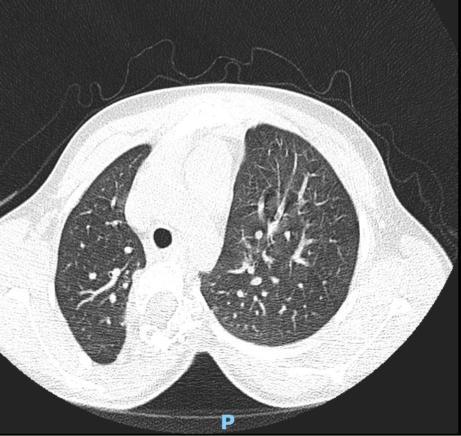

Computed tomography (CT) preoperative planning, identifying congenital vertebral anomalies, or evaluating suspected neoplastic lesions.

Magnetic resonance imaging (MRI) early-onset scoliosis, or in cases of atypical progression, pain, or as part of surgical planning.